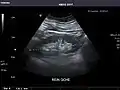

Right kidney

Kidneys: Right and left kidneys measure 11.5 cm and 12 cm in length respectively. No hydronephrosis. Small left lower pole kidney cyst.

Renal ultrasonography

Ultrasonography of the kidneys is essential in the diagnosis and management of kidney-related diseases. The kidneys are easily examined, and most pathological changes in the kidneys are distinguishable with ultrasound.[7]